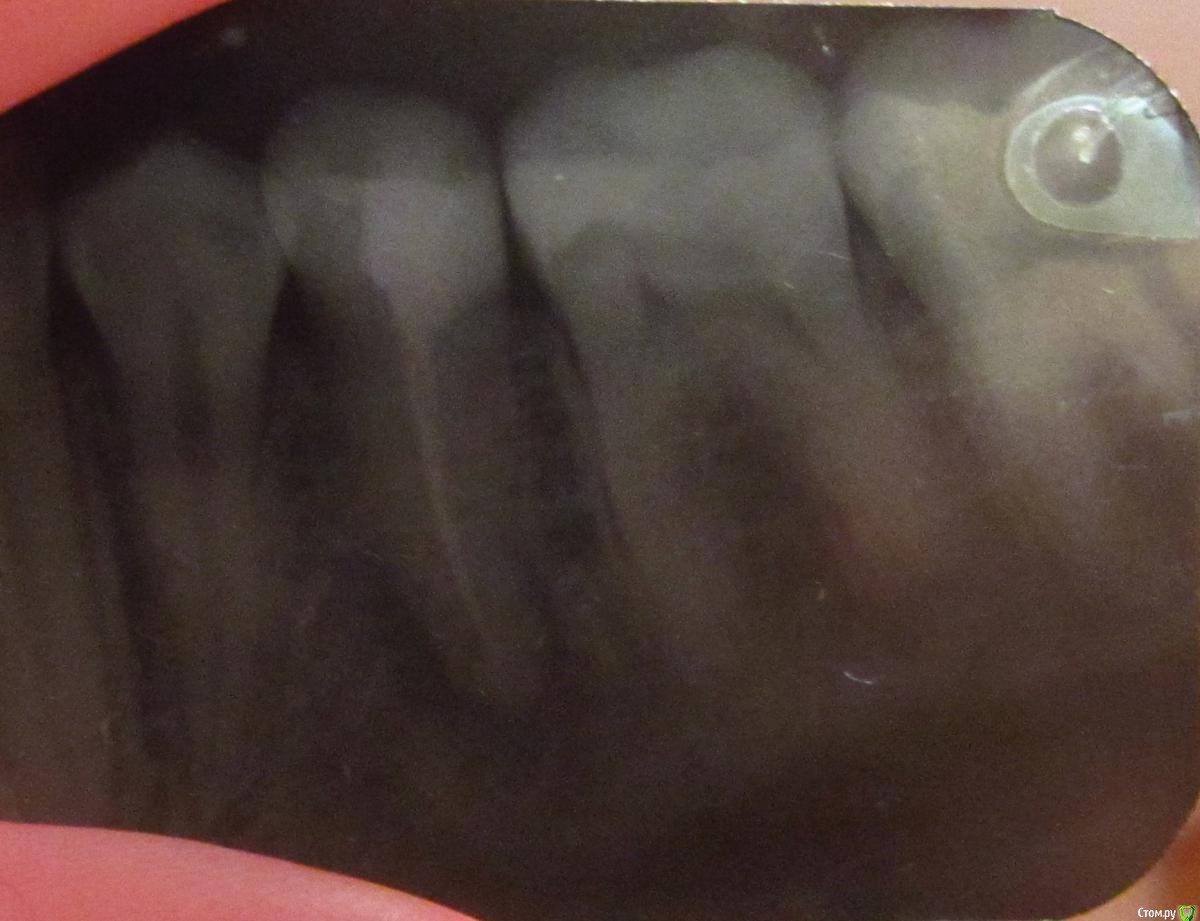

aqua1 Опубликовано 8 февраля, 2015 Поделиться Опубликовано 8 февраля, 2015 Добрый день! История моя давняя и до сих пор не решена….Где-то в 2007 году удалили в нижней 5-ке нерв, но зуб иногда «простреливал» при случайном накусывании по ночам. Подозреваю, что неудачное лечение могло быть связано с тем, что немного передержали лекарство, так как врач был в отпуске..Через полгода, в 2008 году на десне между 5 и 6 образовался бугорок, снимок показал воспаление на корне. Так как каналы на снимке были запломбированы хорошо, сказали что нет смысла их перелечивать, и зуб придётся удалить(( Естественно, меня такой поворот не устраивал, зуб был хорошо сохранен, никогда не беспокоил, и лечение кариеса изначально было просто профилактическим, но канал оказался слишком близко... Второй вариант был антибиотики, образовался свищ, а вскоре всё зажило и припухлость полностью спала (хотя на снимке 2009 года ситуация не изменилась).Ни зуб, ни дёсны не беспокоили меня абсолютно до весны 2012 года, когда после ветреной погоды, зуб поныл 2 дня и образовалась даже не припухлость, а затвердевшая дуга вдоль 6-8 зубов. Боли и воспаления не было. Испугавшись, что это будет расти и дальше такими же темпами, поехала в стоматологию, где терапевт отправила меня к хирургу, у которого было 2 варианта – резать или вырывать. На новом снимке никаких изменений опять замечено не было.. Десну разрезали между 5 и 6, гноя не было, потом отёк сошёл, а затвердение нет.В настоящий момент оно особо не беспокоит, только иногда ощущается в челюсти, асимметрии лица тоже вроде не заметно. В 2014 году начала активно лезть полулежачая восьмерка, без боли и воспаления. Затвердевшая дуга на десне начинается под 6-м зубом и плавно уходит за эту 8-ку. По случаю всего этого в январе 2015 сделали панорамный снимок всей этой красоты.Очень нужны ваши советы!1) Обязательно ли удалять эту 5-ку или как её лечить? Сойдет ли затвердение на десне после удаления? Что это вообще может быть?2) Я так понимаю, что 8-ка на удаление. Стоит ли немного подождать, пока она вылезет побольше, чтобы легче её удалить?Заранее спасибо. Прилагаю всю историю в рентгенах, а также фото, как это выглядит сейчас вживую. Ссылка на комментарий

aqua1 Опубликовано 8 февраля, 2015 Автор Поделиться Опубликовано 8 февраля, 2015 (изменено) Разъяснения по снимкам:1) весна 2008 года - начало2) 2009 год3) весна 2012 года - сразу после обострения и появления отвердевшей десны4) свежий снимок 2015 года5) так выглядит зуб мудрости4) зубы и десна в обычном состоянии7) и 8) - изображения отвердевшей дуги на десне вдоль 6, 7 и 8 зубов (т.е. та область, что между зубами и пальцем) Изменено 8 февраля, 2015 пользователем aqua1 Ссылка на комментарий